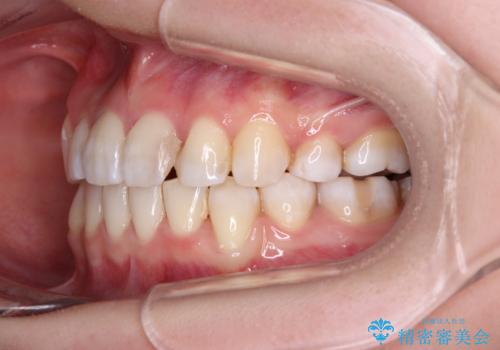

- 上下の八重歯と前歯のデコボコを気にして来院された患者様です。

右上と左下の八重歯が特に著しく、上顎正中が右側にシフトしていました。

八重歯のためずれていた上下の正中をほぼ一致する位置に整えることができました。

重なって汚れの溜まりやすかった部分も改善され、大変満足していただけました。